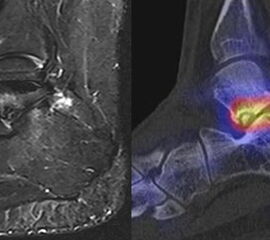

Abbildung 2.2.

Bilder eines Patienten mit Z. n. mehrfachen Sprunggelenksdistorsionen in der Vergangenheit, besonders heftige Distorsion des linken Sprunggelenkes 5 Wochen vor der Untersuchung. Die SPECT/CT zeigt eine instabile osteochondrale Läsion mit deutlicher Aktivierung.

Zum Lesen der Bildbeschreibung und zur Vollansicht bitte das Bild anklicken. Bild: H. C. Rischke